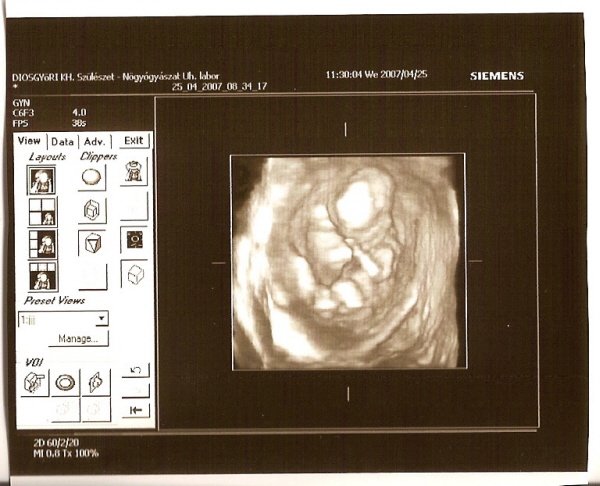

Okr! Nagyon szép a babád! Az enyém is nagyon mocorgott, amikor a 12 hetesen voltunk :) Ásítozott meg boxolt :D

Tegnap voltam uh.-n próbáltuk 100%.-ra megnézni, a babát, hogy biztosan fiú- e, mert a múltkor csak90%.- ra mondta a szanográfus, csak sajna aludt a baba, összekúlcsolt felhúzott lábakkal, az istennek sem akarta megmutatni magát.

Csak egy pillanatra láttunk egy fütyi szerűséget, úgyhogy még mindíg kisfiú. :D :D :D :D

De kaptam egy aranyos képet felrakom nektek.